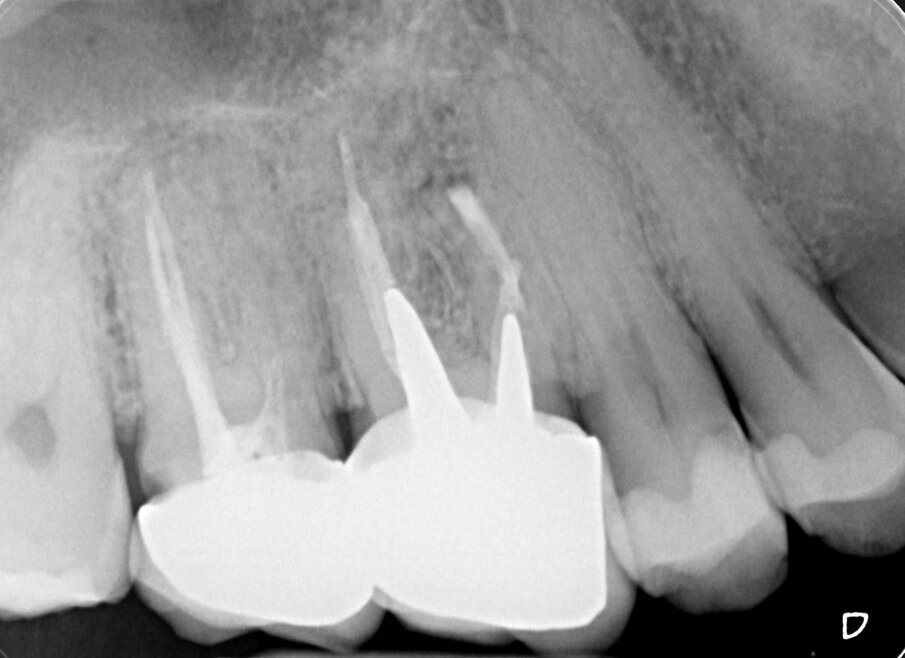

Fig. 2a - Radiografia preoperatoria del secondo molare superiore di sinistra. La paziente lamenta dolore alla masticazione su questo dente, trattato endodonticamente pochi mesi prima. La stessa viene indirizzata con la specifica richiesta di eseguire la terapia chirurgica e di non aprire una cavità d’accesso, allo scopo di non sciupare la “nuova” corona ceramica da poco cementata.

Fig. 2b - Una piccola lesione è evidente all’apice della radice mesiovestibolare.

Fig. 2c - La CBCT mostra l’inclinazione distale della radice distovestibolare del primo molare.

Fig. 2d - La sezione coronale mette in evidenza il fatto che la radice distovestibolare del primo molare è vestibolare alla radice mesiovestibolare del secondo molare.

Fig. 2e - Le quattro sezioni assiali mostrano come la radice distovestibolare del primo molare sia vestibolare rispetto alla radice mesiovestibolare del secondo molare. Questa particolare situazione anatomica rappresenta una ovvia controindicazione all’approccio chirurgico.